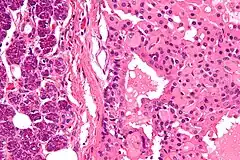

![]() Oncocitoma que afecta a la glándula parótida. | ||

Es poco frecuente, representa únicamente el 1% de los tumores que afectan a la glándula parótida. Se presenta como una masa no dolorosa superficial que muy raramente provoca metástasis. Es más habitual en la sexta década de la vida y el tratamiento de elección es la extirpación de la parótida.[6]